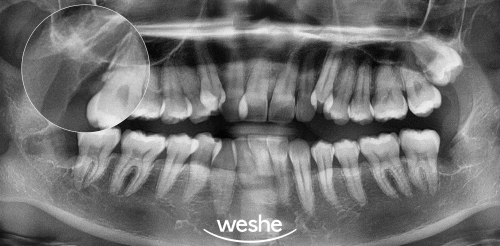

때문에, 방사선 사진을 통해

정확한 위치와 방향을 파악한 후

치료 계획을 세워야 된다

저는 생각합니다😊

이를 빼내는 진료를 진행할 때는

3D-CT를 통해 주위 조직구조의 위치를

정확히 파악한 후

개별화된 계획을 세우는 것이 중요하며,

주위 중요 구조물과 치아에

영향을 주지 않으면서

뿌리 끝까지 빼내는 것이

추후 예후에 좋은데요.

준비한 예시 사진을 보면

남아 있는 치아 뿌리 조각 하나 없이

빼내진 것을 확인할 수 있습니다.